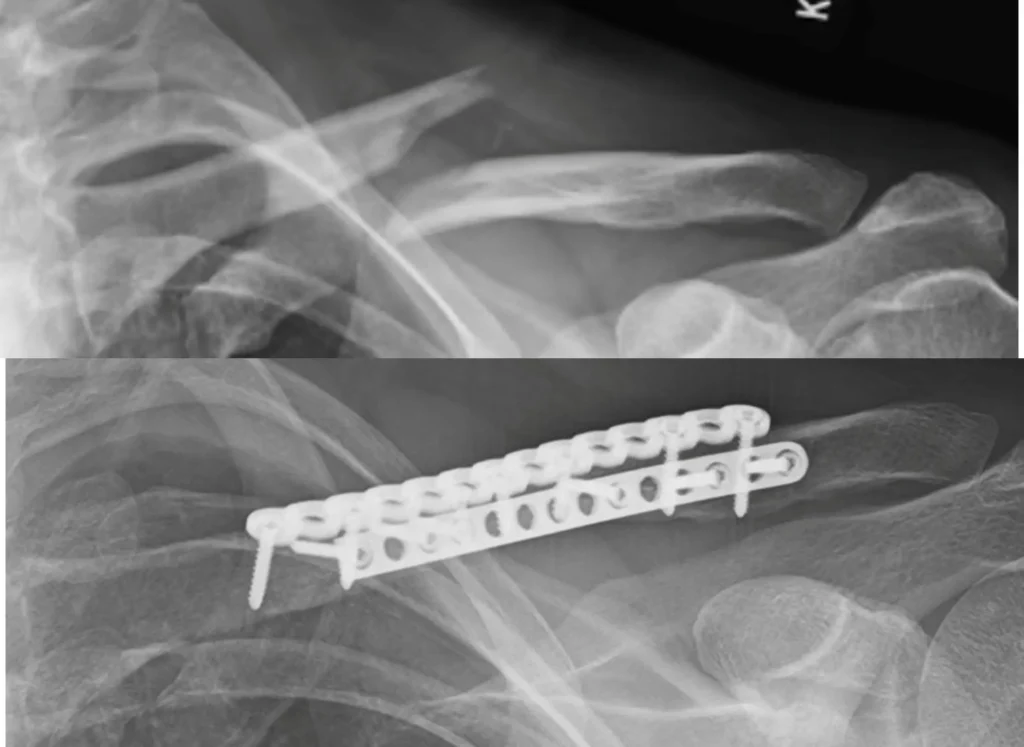

Treatment Imaging

Fracture Care